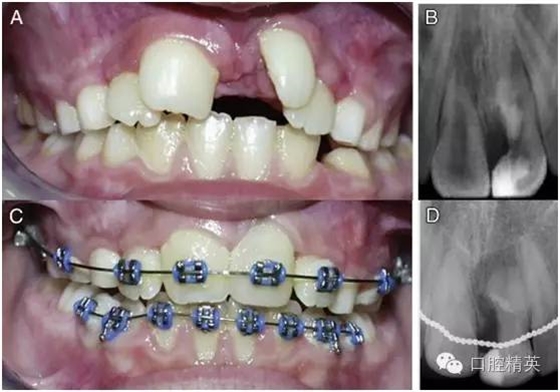

正常隨訪 12 周之后,患牙未出現(xiàn)異常癥狀(圖 3-A),于是按計劃開始對患者進行牙齒的矯正。從骨頭和牙齒來看,患者都表現(xiàn)出了遠中錯頜的關系,按照安氏分類法,患者被診斷為安氏 2 類 1 分類錯頜畸形?;颊哳M骨發(fā)育基本正常,上頜稍后縮,但未出現(xiàn)反頜。上頜切牙區(qū)稍擁擠。

圖 3 正畸前與正畸后期資料。(A)正畸前口內像,此時多生牙部分已被切除,露髓處已經(jīng) MTA 蓋髓,且正常隨訪一段時間后未見其他異常癥狀出現(xiàn)。(B)正畸前患牙根尖片。(C)正畸治療將要結束時的口內像,此時患牙牙冠已經(jīng)參照右上中切牙用復合樹脂進行了美學修復。(D)正畸后患牙根尖片。

整個正畸過程持續(xù)了 3 年半(圖 3-C)。正畸完成治療后,為了獲得最終的美學效果,患牙剩余部分參照右上中切牙的外形和顏色用樹脂做了充填修復(圖 3-C)。將術前根尖片(圖 3-B)與正畸后根尖片(圖 3-D)相比較可以發(fā)現(xiàn),患牙最終表現(xiàn)出了良好的治療效果。